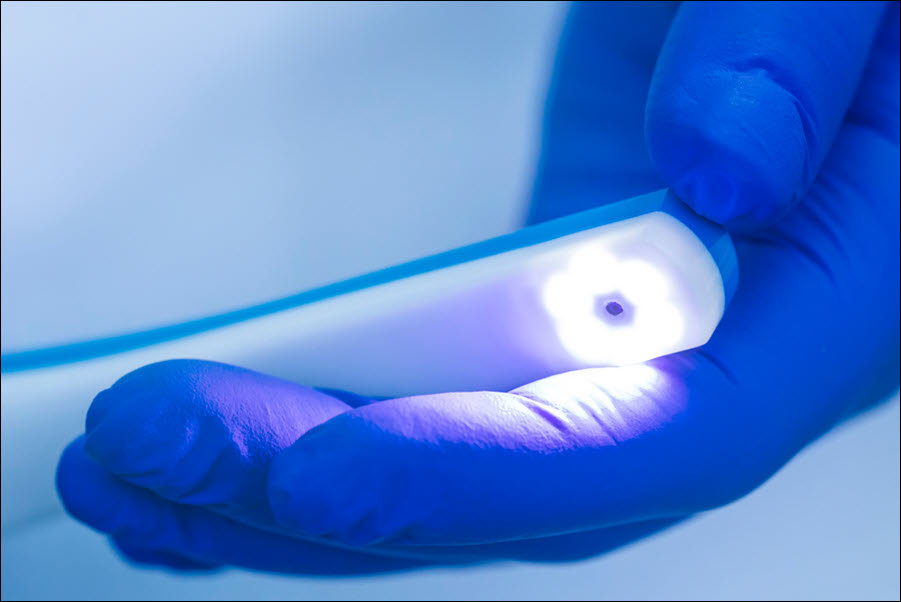

The sealant process is simple and noninvasive. First, we clean the tooth thoroughly to remove plaque and debris. Next, we gently prepare the chewing surface so the sealant can bond properly. A thin, protective resin is then painted onto the grooves of the tooth and hardened with a special curing light. Once set, the sealant forms a smooth barrier that helps block bacteria and makes the tooth easier to keep clean with normal brushing.